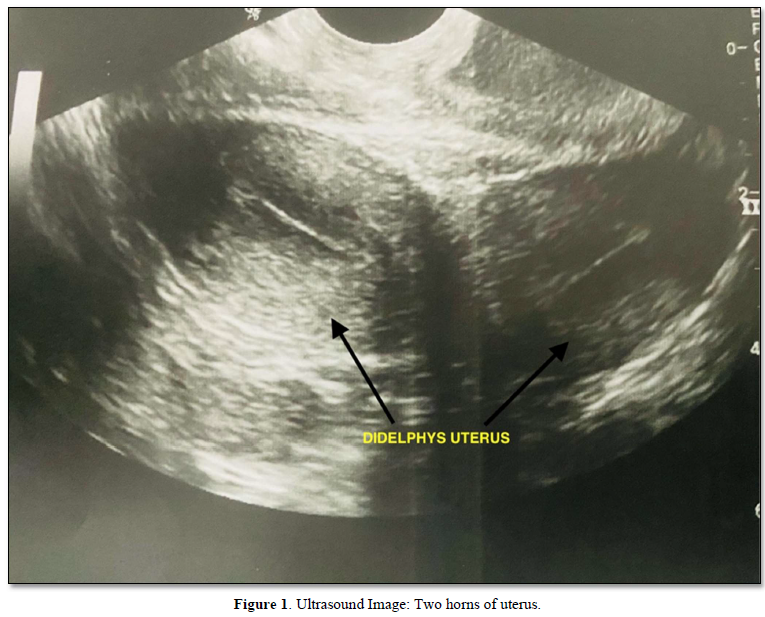

A 13-year- old female presented with complaints of dysmenorrhea and menorrhagia for the past 7 months. She attained menarche 7 months ago and had cycles every 20 days with 7-8-day duration. General examination showed good general condition with no pallor. Abdominal examination was within normal limits. Laboratory tests including complete blood count and thyroid profile were normal. Ultrasound showed a bicornuate uterus with normal echo pattern with a well-defined hypoechoic collection of size 5X5 cm in right sided cervix (Hematocolpos) with normal ovaries. The right kidney was not visualized (Figure 1).